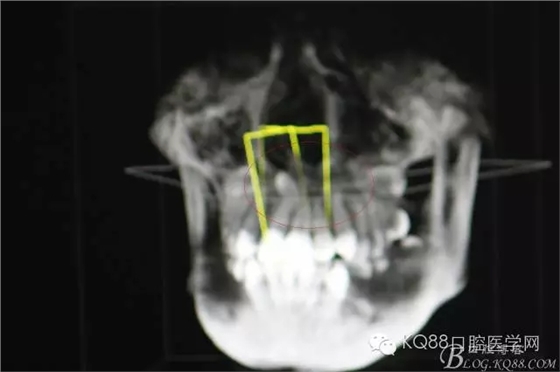

圖3.CBCT三個方向剖面圖影像:多生牙牙根阻擋11內收、牙冠接近鼻底

圖4.cbct的三維重建影像:多生牙牙尖幾乎和鼻底相通